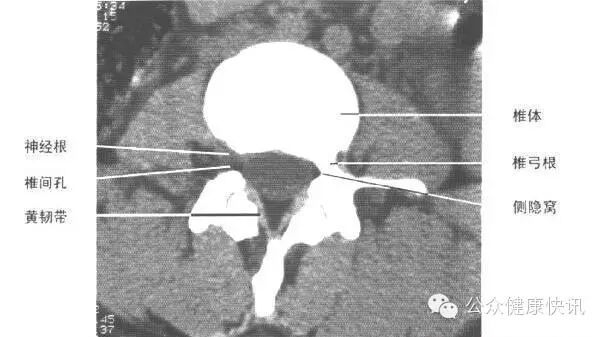

这是腰椎CT正常情况

CT

用X线给身体每个横截面“拍照”

特长:成像比X线更清晰;对高密度的骨性组织和出血、肿瘤的钙化病变的检出,具有独特优势。低剂量的螺旋CT是对肺癌筛查的有效手段。